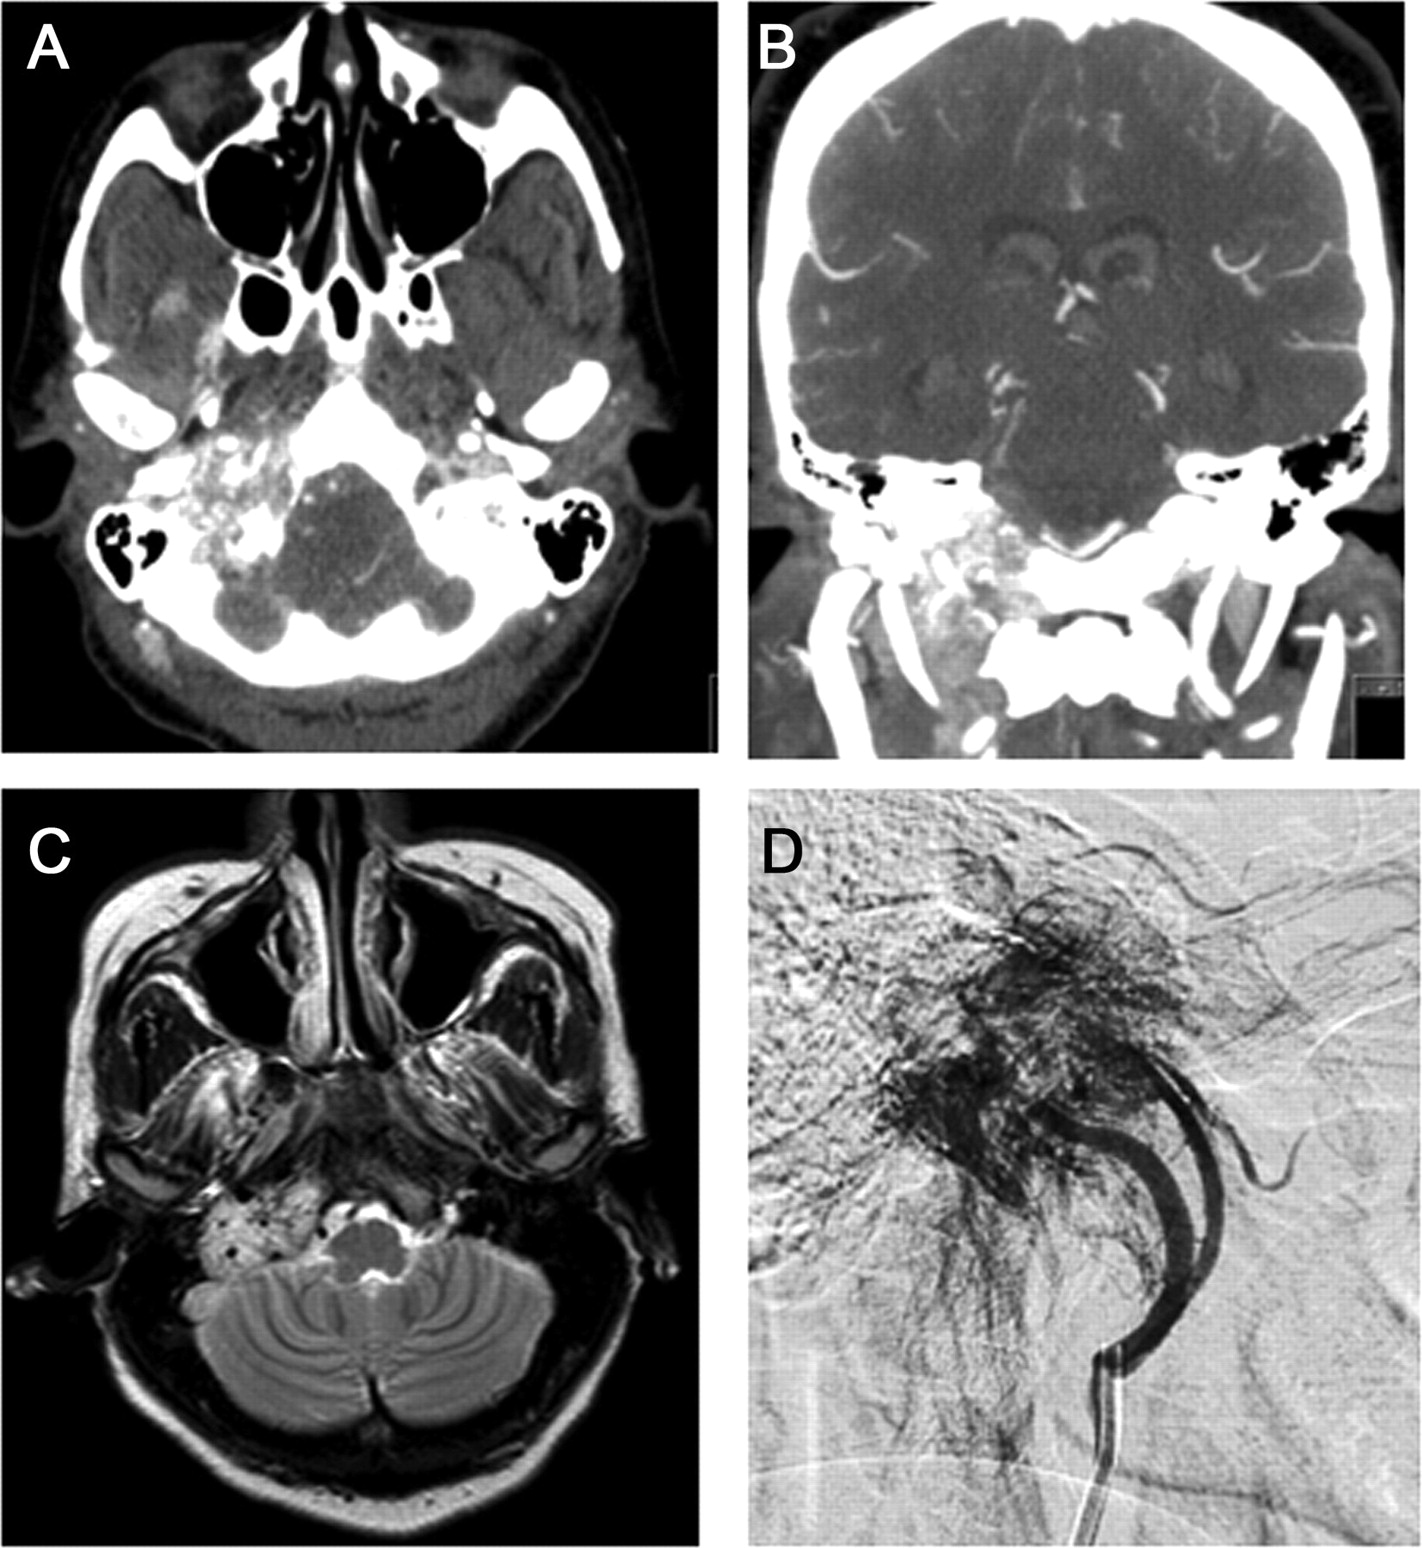

术前栓塞后右颈外动脉喂食器,病人接受经岩/颞颥骨下的窝肿瘤切除的方法。一个大红色的质量被认为中耳内的空间与大量的扩展通过颅底和颅内。通过颈静脉孔肿瘤扩展,有相当大的侵蚀的岩石的颞骨的顶点。颅内肿瘤毗邻的横向部分降低脑桥和髓质。有几个大型的前下小脑动脉动脉喂食器。颈内静脉大大膨胀与肿瘤扩展几厘米下级内部的腔静脉。肿瘤的这一部分被全体测量8.0厘米,1.7厘米,0.8厘米。腊肠形出血性肿瘤与凝胶状的外观,切割面观察了齐次tan粉红色的外观(图3A和B)。其余的肿瘤被零碎的时尚。访问所需的肿瘤面部神经改道的。肿瘤转移附近舌咽神经、迷走神经、脊髓配件,和舌下神经。

(A, B)的部分质量从颈静脉腔内发现了一个肿瘤,8厘米×1.7厘米×0.8厘米,谭粉红色切割面。质量的显微照片(C,苏木精和伊红)揭示了一个高度血管化肿瘤与肿瘤细胞巢(zellballen)隔开小血管。(D) CD34染色突显出血管。(E)扩散chromogranin免疫反应性。(F)分散S100-positive细胞(支撑的细胞)。

显微镜下,肿瘤血管(很图3C和D)。肿瘤内部的血管将细胞分成不规则组织造成zellballen模式(图3C和D),血管明显由CD34染色(图3D)。主要的细胞被chromogranin积极(图3E)和synaptophysin(没有显示)。支撑的细胞被S100积极(图3F)。解剖诊断jugulotympanic副神经节瘤。手术后,她立即耳鸣解决。病人开发了新的面部从面部神经改道的弱点,继续改善。她的高血压也有所改善,但并没有完全解决。